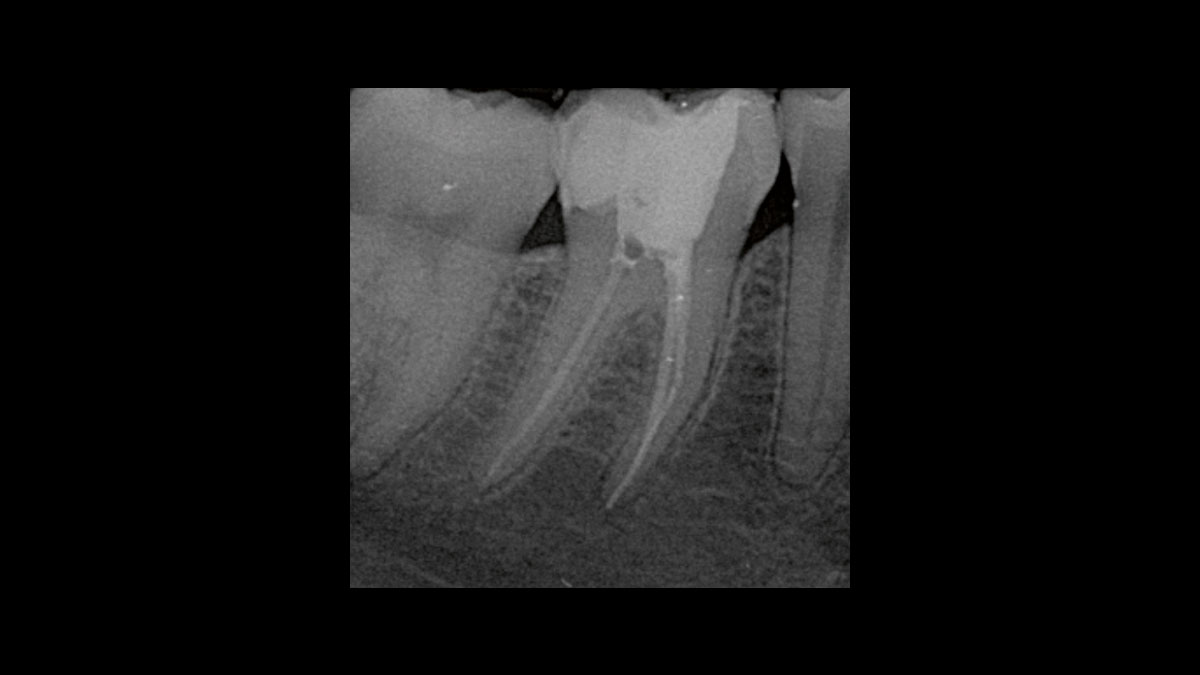

Эндодонтия

На видео и изображениях представлены следующие варианты применения:

• Подавление микробной контаминации в эндодонтии

• Подавление микробной контаминации при омертвении

Подавление микробной контаминации в эндодонтии